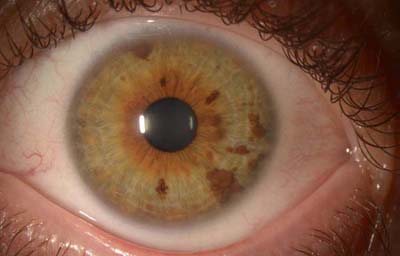

Hamartomas - Nódulos de Lisch. Son estructuras benignas, nodulares, de aspecto gelatinoso, implantadas con pedículo sésil sobre la superficie de la hoja anterior del Iris, compuestas por proliferación de células histológicamente maduras, de origen melanocítico normales del tejido en el que residen, de color que varía del castaño claro al castaño oscuro y generalmente de ± 1.0mm. Cuando se asocian a la Neurofibromatosis de Von Recklinghausen, se las considera patogneumónicas y se las denomina nódulos de Lisch (24, 25,26)

Hamartoma del Iris

Archivo Fotográfico Dr. Carmen Barraquer.

Nódulos de Lisch

Archivo Fotográfico Dr. Francisco Barraquer.

Nódulos de Lisch

Archivo Fotográfico Dr. Francisco Barraquer.